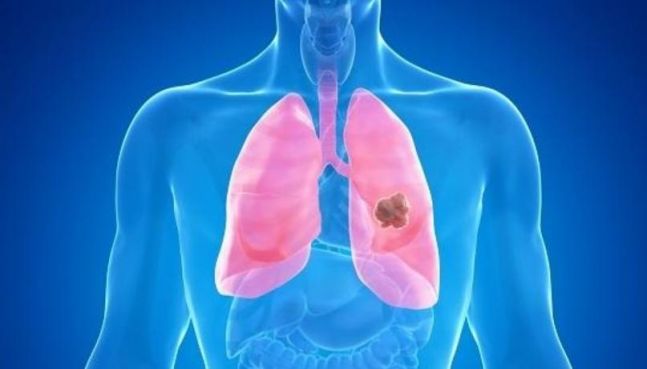

근데 그중에서도 양성으로 우리가 이제 주목해도 되는 혹도 있고 악성으로 돼서 소칭 말하는 우리가 암이라고 사색하는 폐에서 만들어 낸 원발 종양을 폐암이라고 하고요.

안녕하세요. 폐암은 다들 이제 잘 알다시피, 폐에 생기는 악성 종양을 말하더라고요. 폐의 결절이라서 많이들 진료를 보러 오시는데 폐 결절은 폐 생기는 혹이나 덩어리를 의미하고요.